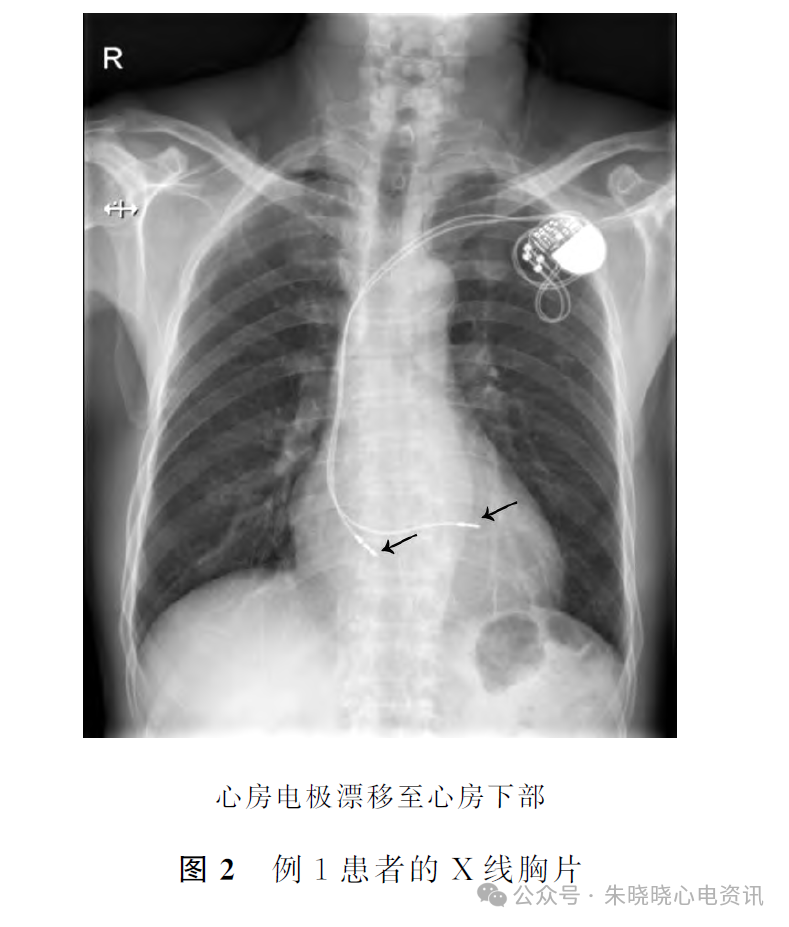

④心房起搏P′波倒置,提示心房电极脱位漂移至心房下部,请拍胸片.患者行胸片检查明确心房电极漂移至心房下部(图2).及时手术调整心房电极位置,术后起搏心电图恢复正常.